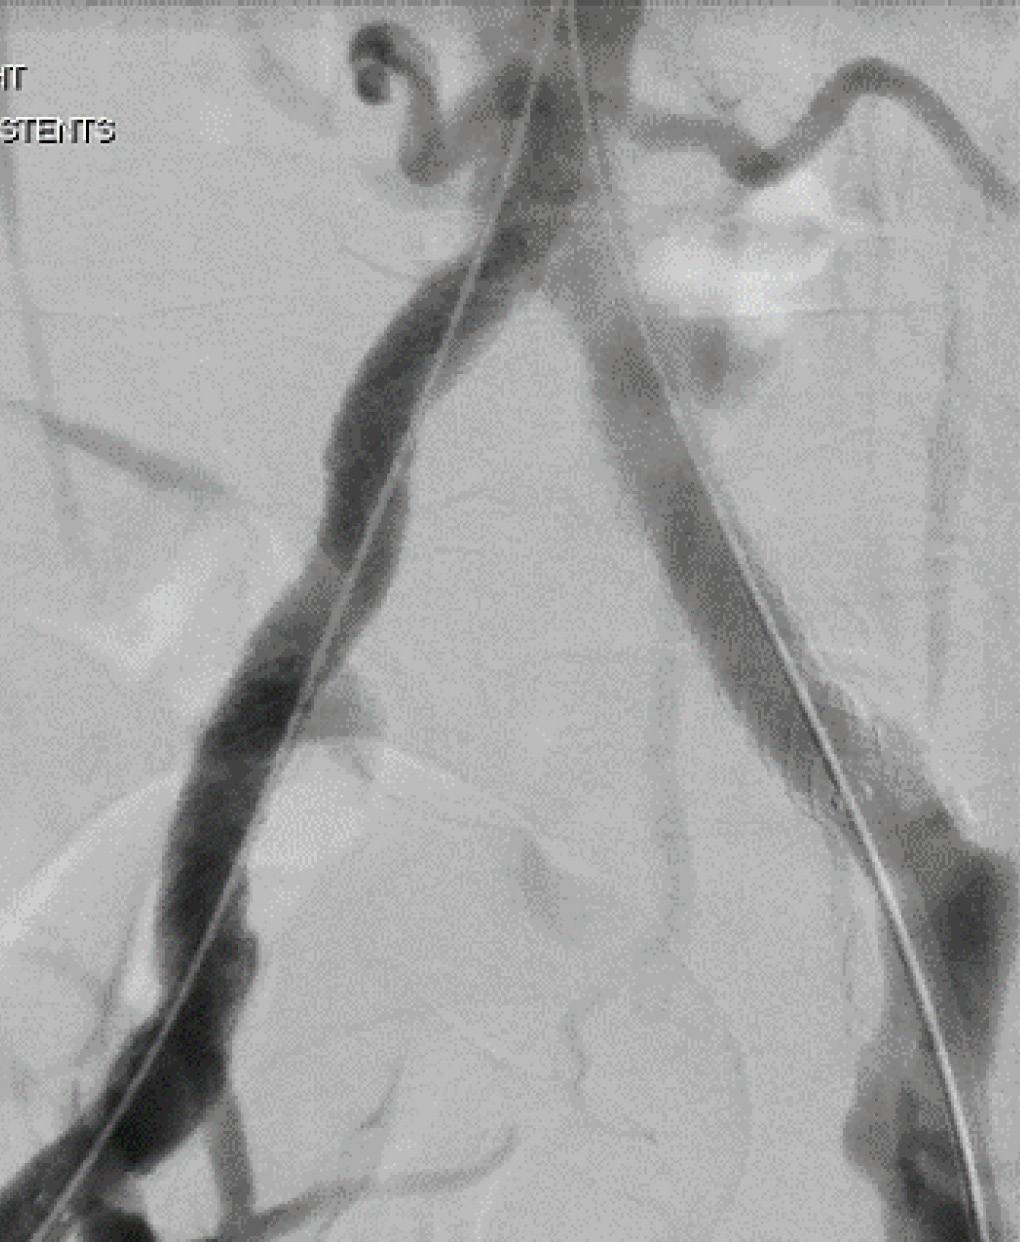

Removing in-stent thrombosis with the RevCore Thrombectomy

Catheter

For patients with in-stent thrombosis (IST), one of the most critical unmet needs has been an effective method to remove acute-to-chronic material. Here, Rishi Roy, MD, a vascular surgeon at Advanced Vascular & Vein Associates in Flowood, Mississippi, discusses his experience with the first mechanical thrombectomy device to be able to do so—the RevCore thrombectomy system. RevCore is a minimally invasive, over-the-wire device indicated to treat thromboemboli in the peripheral vasculature, including venous stents. It includes a catheter with an expandable element for venous stent treatment. It also has a reinforced catheter shaft for precise movements and a diameter-control knob for adjusting the element to treat vessels 6mmplus and venous stents from 10–20mm.

Prior to RevCore, how did you treat in-stent thrombosis?

Previously I would take a multimodal approach using suction thrombectomy, along with balloon venoplasty, or even a non-compliant balloon. The goal was to get some lumen gain, to restore some outflow to decompress the limb.

How does this new device work?

RevCore makes it possible to extract thrombotic material from an occluded stent. The diameter of the coring element can be increased or decreased manually to accommodate the size of the vessel . You engage or disengage with the stent, as needed, and you can be more aggressive as you work through the material that caused the occlusion.

How do you size the catheter and capture liberated clot?

nal stent diameter, that patient will require close follow-up every six months or so, but they may be able to go for a couple of years between interventions. Fewer interventions also means decreased anesthesia time, operative time, chance of adverse events and morbidity. If we can decrease the number of cases because we’re able to remove IST in a single procedure, that’s a game changer.

Initial IVUS confirmed the IST (A). Preprocedure venogram demonstrated instent thrombosis and impaired flow (B). Extracted thrombotic material (C). Postprocedure IVUS confirms stent patency (D). Postprocedural venogram confirms patency (E). RevCore Thrombectomy Catheter with expandable coring element (F)

is new, I have an intensive follow-up protocol and, working with a wound care group, even closer follow-up is possible. I generally see the patient back in four weeks. After that, we see them at three and six months, and then every six months. If over a twoyear period we don’t see recurrent stenosis, and the patient is comfortable, we could get it down to once a year.

What anticoagulation regimen do you give these patients?

Case report: Complete thrombus extraction after severe right EIV stent stenosis

Patient history

When sizing the element in the stent, low and slow is key. There is a tactile feel to the device when “revving,” and it’s important to note resistance level. Some resistance is good—too much means the element is likely oversized and should be decreased by turning the external diameter-control knob to the minus sign on the handle. An important consideration for these cases is to have another device placed in the inferior vena cava (IVC) to capture the cleared material.

When do you know that RevCore worked?

Immediately postprocedure, I can gauge whether the device worked when I visualize blood flow on imaging. Because the device

I send them out on either a novel oral anticoagulant (NOAC) or Coumadin. You know, people often ask me, “Which do you prefer?” My honest answer is I prefer whatever the patient can afford. Because if they can’t afford a NOAC, then they’re not going to take it, and we’re back at square one.

How do you think RevCore will change the treatment pathway?

RevCore allows us to consider intervention sooner for patients who are suffering from symptoms related to IST. Some had stents placed when they were in their 20s or 30s, and when these stents are put in, they’re in forever. Now it’s decades later, and they have recurrent IST with chronic material that requires reintervention every threesix-eight months for symptom relief. Now, if we can debulk and get back to the origi-

A FlowTriever catheter (Inari Medical) was advanced over a stiff wire to the infrarenal segment of the IVC, and two of the catheter’s XL disks were deployed. From the right side, a stiff wire was advanced to the IVC via a Bern catheter (Boston Scientific), followed by an Amplatz wire. The catheter was removed, and then a 16F sheath was placed.

IVUS was performed in the IVC, revealing that the stent extended into the very distal IVC; no stenosis was seen. IVUS of the right common iliac vein (CIV) showed overlapping stents but no stenosis. A venous ultrasound probe inserted to the level of the right EIV showed 50–60% stenosis. IV heparin was administered.

The RevCore catheter was advanced over the Amplatz wire to the right EIV, and the coring element was deployed within the stent in an unexpanded state. The coring element was then slowly enlarged and rotated, loosening the material within the stent. RevCore was then withdrawn and cleaned. A Triever16 Curve catheter (Inari Medical) was advanced and suction thrombectomy performed, removing a combination of subacute and chronic thrombotic material (C). Balloon venoplasty of the stented portion of the right CFV, EIV and CIV was performed with an 18mm noncompliant balloon.

Additional passes with the Triever16 Curve catheter were conducted along the right iliac segments and within the IVC, removing thrombotic material that had been captured by the FlowTriever XL disks. Thrombus capture with either FlowTriever XL disks or the Protrieve sheath is critical to the RevCore procedure. Blood was returned to the patient using FlowSaver.

A man in his mid-50s presented with ulceration and swelling in his right foot with the intention to transfer care. Several months prior, a right external iliac vein (EIV) to right common femoral vein (CFV) stent had been placed. A venous duplex ultrasound study showed proximal stent occlusion and non-occlusive venous thrombosis in the left proximal femoral, popliteal, posterior tibial, and gastrocnemius vessels, as well as thrombosed varicosities. Right lower extremity venography and intravascular ultrasound (IVUS) performed two-and-a-half weeks later confirmed 65% stenosis of the left EIV stent (image A). An in-hospital mechanical thrombectomy and balloon angioplasty procedure was planned.

Procedural overview

The patient was positioned supine and ultrasound guidance was used to access the right CFV. A J-wire was advanced into the IVC. An 8F sheath was placed and a venogram showed stenosis within the right EIV stent (B). Similarly, access was gained to the left CFV, and a J-wire was advanced into the IVC. An 11F sheath was placed and a venogram confirmed there was no stenosis in the selected segments.

A final IVUS showed nearly 100% lumen gain, restoring the right EIV to CFV in-stent diameter to 16.4 mm (D). A final venogram demonstrated appropriate flow through the right CFV, EIV, CIV and IVC, and resolution of the stenosis within the right EIV (E). The FlowTriever disks and all other devices were removed, and manual pressure was held.

Total procedure time: 40 minutes. Estimated blood loss: <50mL. The patient tolerated the procedure well. He was discharged on dabigatran the following day. At four-week follow-up, stent patency was maintained per venous duplex ultrasound, and the patient’s right lower extremity pain and edema had improved. Progress was also seen in a previously non-healing ulceration of the right foot.

He will continue wound care and daily medication and return every six months for repeat imaging.

Conclusion

Use of the novel RevCore system ( F) allowed for thorough extraction of in-stent thrombosis and complete lumen restoration post-thrombectomy, with sustained patency and symptom relief at follow-up. The results show promise for improving quality of life in patients who had exhausted their treatment options previously.